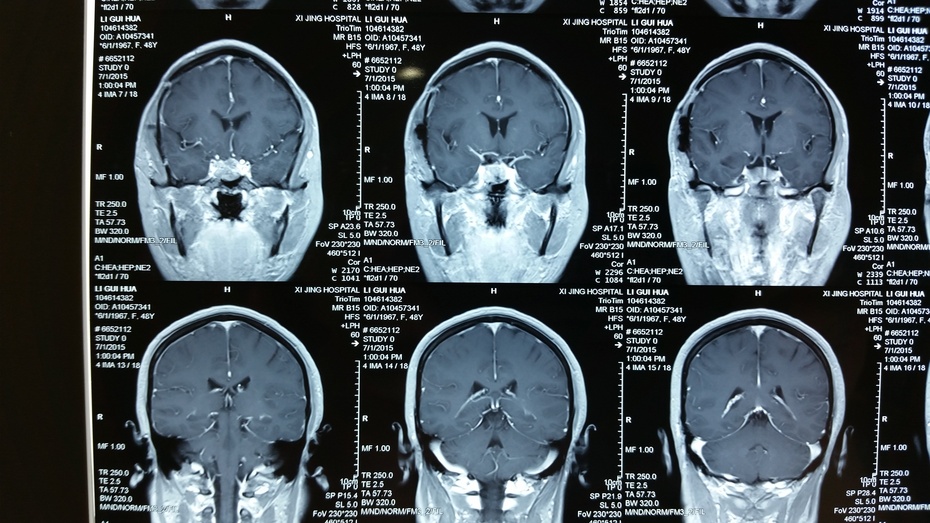

【病例】不典型的垂体瘤1例mr影像表现

肿瘤为无功能性肿瘤,不分泌内分泌激素,影像学提示垂体肿瘤往鞍上生长

垂体瘤的影像诊断

垂体瘤的mr诊断与鉴别诊断

侵袭性垂体瘤的mri 征象